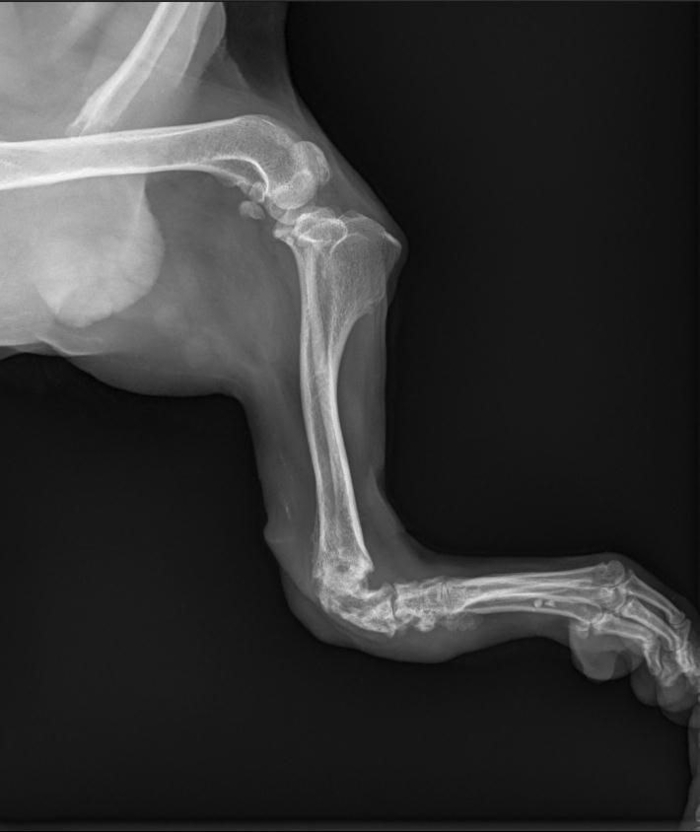

Ветеринары провели ряд исследований, чтобы определить необходимость операции.

- Владимир Александрович, врач из Санкт-Петербурга, изучил снимки компьютерной томографии, – сообщила владелица приюта. - Операция на лапе возможна.